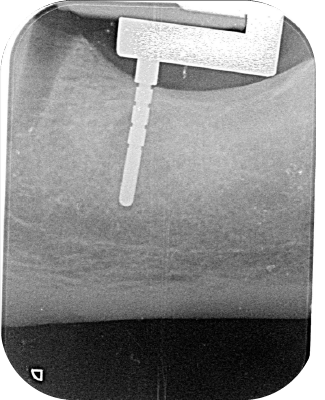

Periapical radiographs are very accurate as long as the depth probe and the film are parallel and the central beam is perpendicular to both. This is practically impossible to achieve during surgery.

By fitting Sniper Xray to conventional film holder allows for consistent orthogonal radiographs and greater measurement precision.

Preliminary testing conducted by oral and maxillofacial radiologists at the University of Texas – San Antonio demonstrated Sniper Xray’s ability to maintain consistent projection geometry and deliver high precision in intraoperative periapical imaging.